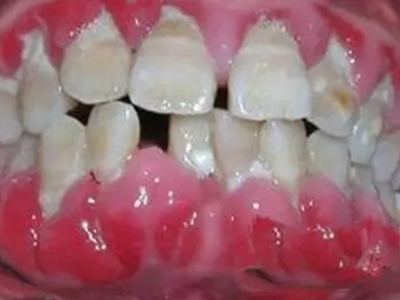

急性坏死性溃疡性龈炎起病急,病程短,常为数天至1-2周,以龈乳头和龈缘的坏死为其特征性损害,尤以下前牙多见,初起时龈乳头充血水肿,个别龈乳头顶端可发生坏死性溃疡,上覆有灰白色坏死物,中央凹下如火山口状。龈缘如虫蚀状,坏死区出现灰褐色假膜,擦去后可见出血创面。龈乳头被破坏后与龈缘成一直线,如刀切状。病损一般不波及附着龈,患处牙龈极易出血,疼痛明显并有腐败性口臭。

重症患者可有低热、疲乏等全身症状,并可伴有下颌下淋巴结肿大和压痛。有的患者可能进展为坏死性龈口炎、坏死性溃疡性牙周炎等疾病,从而导致牙周袋形成、牙槽骨吸收和牙齿松动。